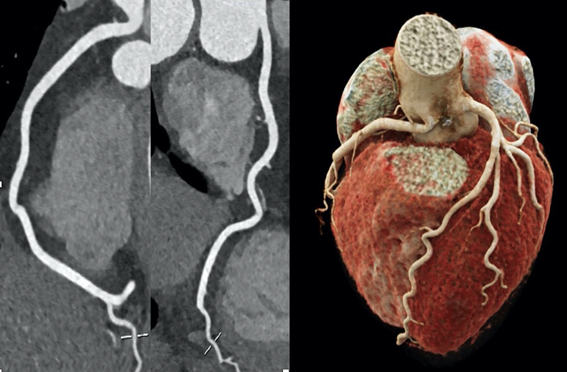

CT Coronary Angiogram

Angio-TC coronariana, destacando a visualização de vasos cardíacos. Fonte: Unsplash

• Cardiologia: Angio-TC para avaliação de artérias coronárias.